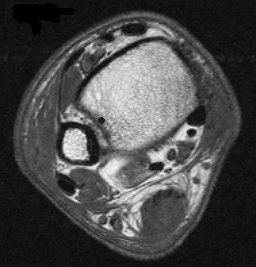

12251.jpg (12881 bytes) 12287.jpg (14606 bytes)